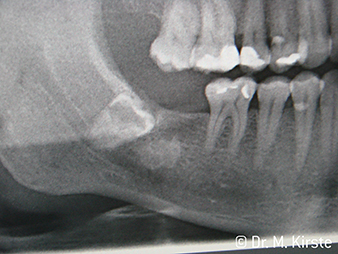

Zdj. 6:

Przypadek: Zatrzymany ząb...

Zdj. 7:

... sprawnie usunięty przy użyciu nowej kątnicy